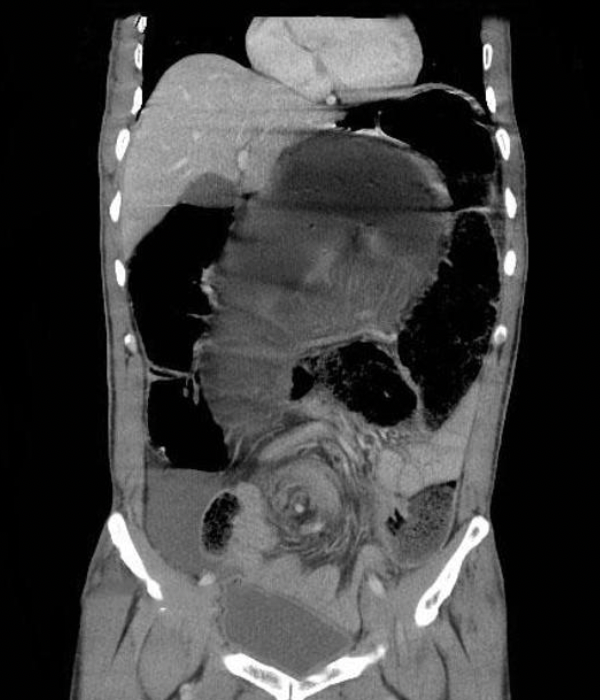

intussusception

target sign

target sign or bulls eye